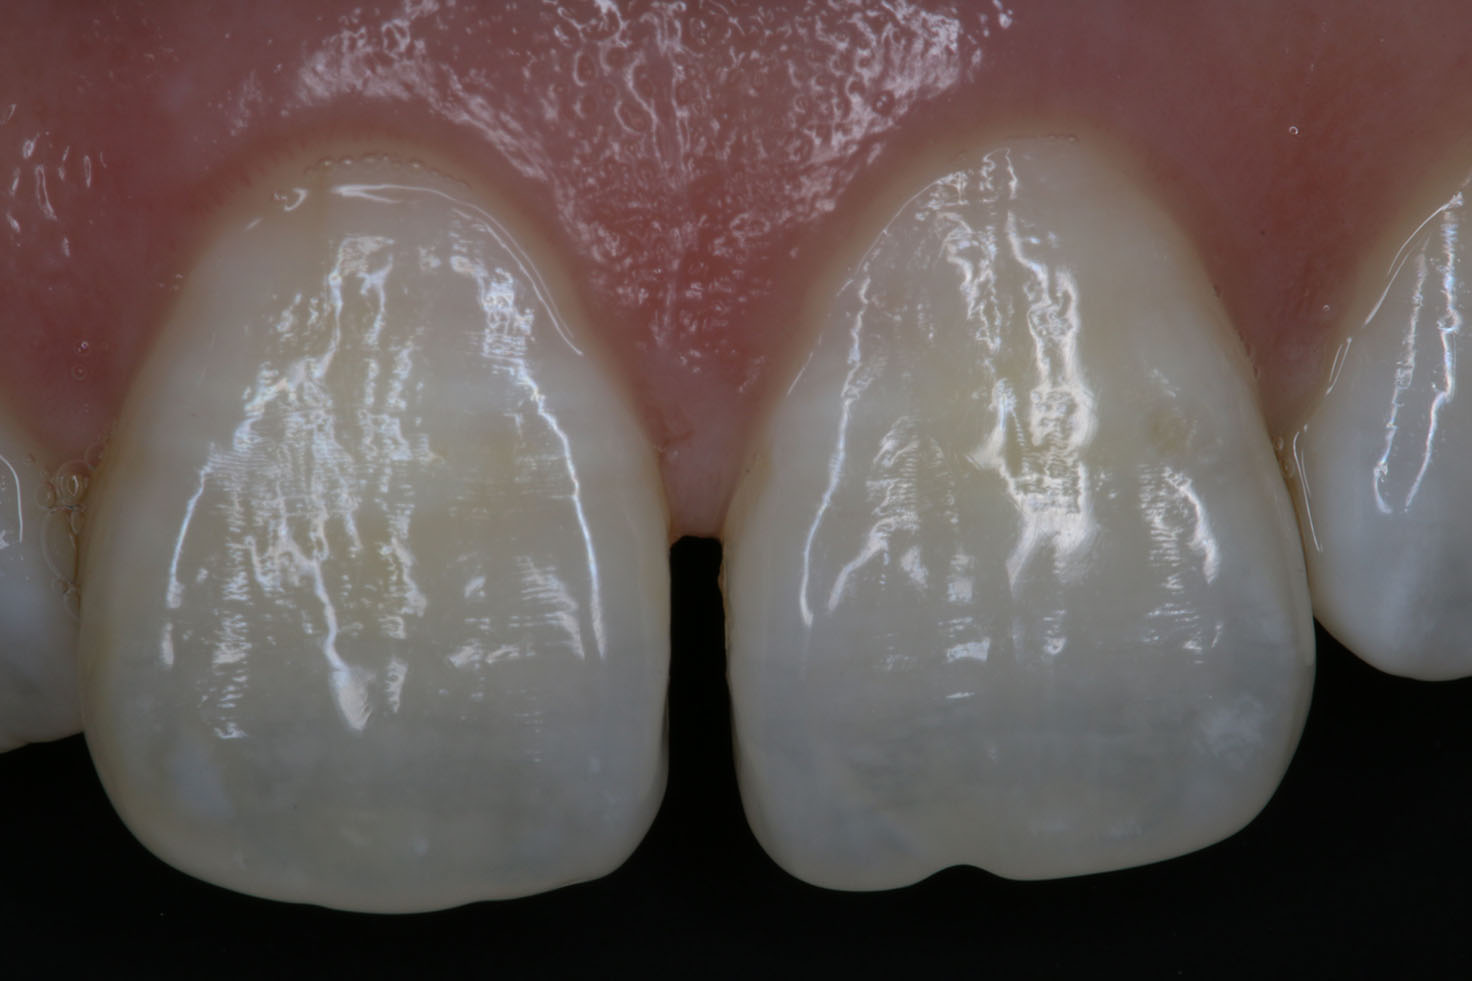

Trauma Case.

The patient had an accident and broke her lower front tooth. We put the fragment back and it looks just as nothing happened.

Tooth Fragment.

For a regular dentist, this may take 2 -3 appointments to fix, more tooth structure loss due to crowning, and might cost thousands of dollars. However, with Dr. Tao's expertise, such problems can be easily fixed with accuracy and high-quality in as little as one day.